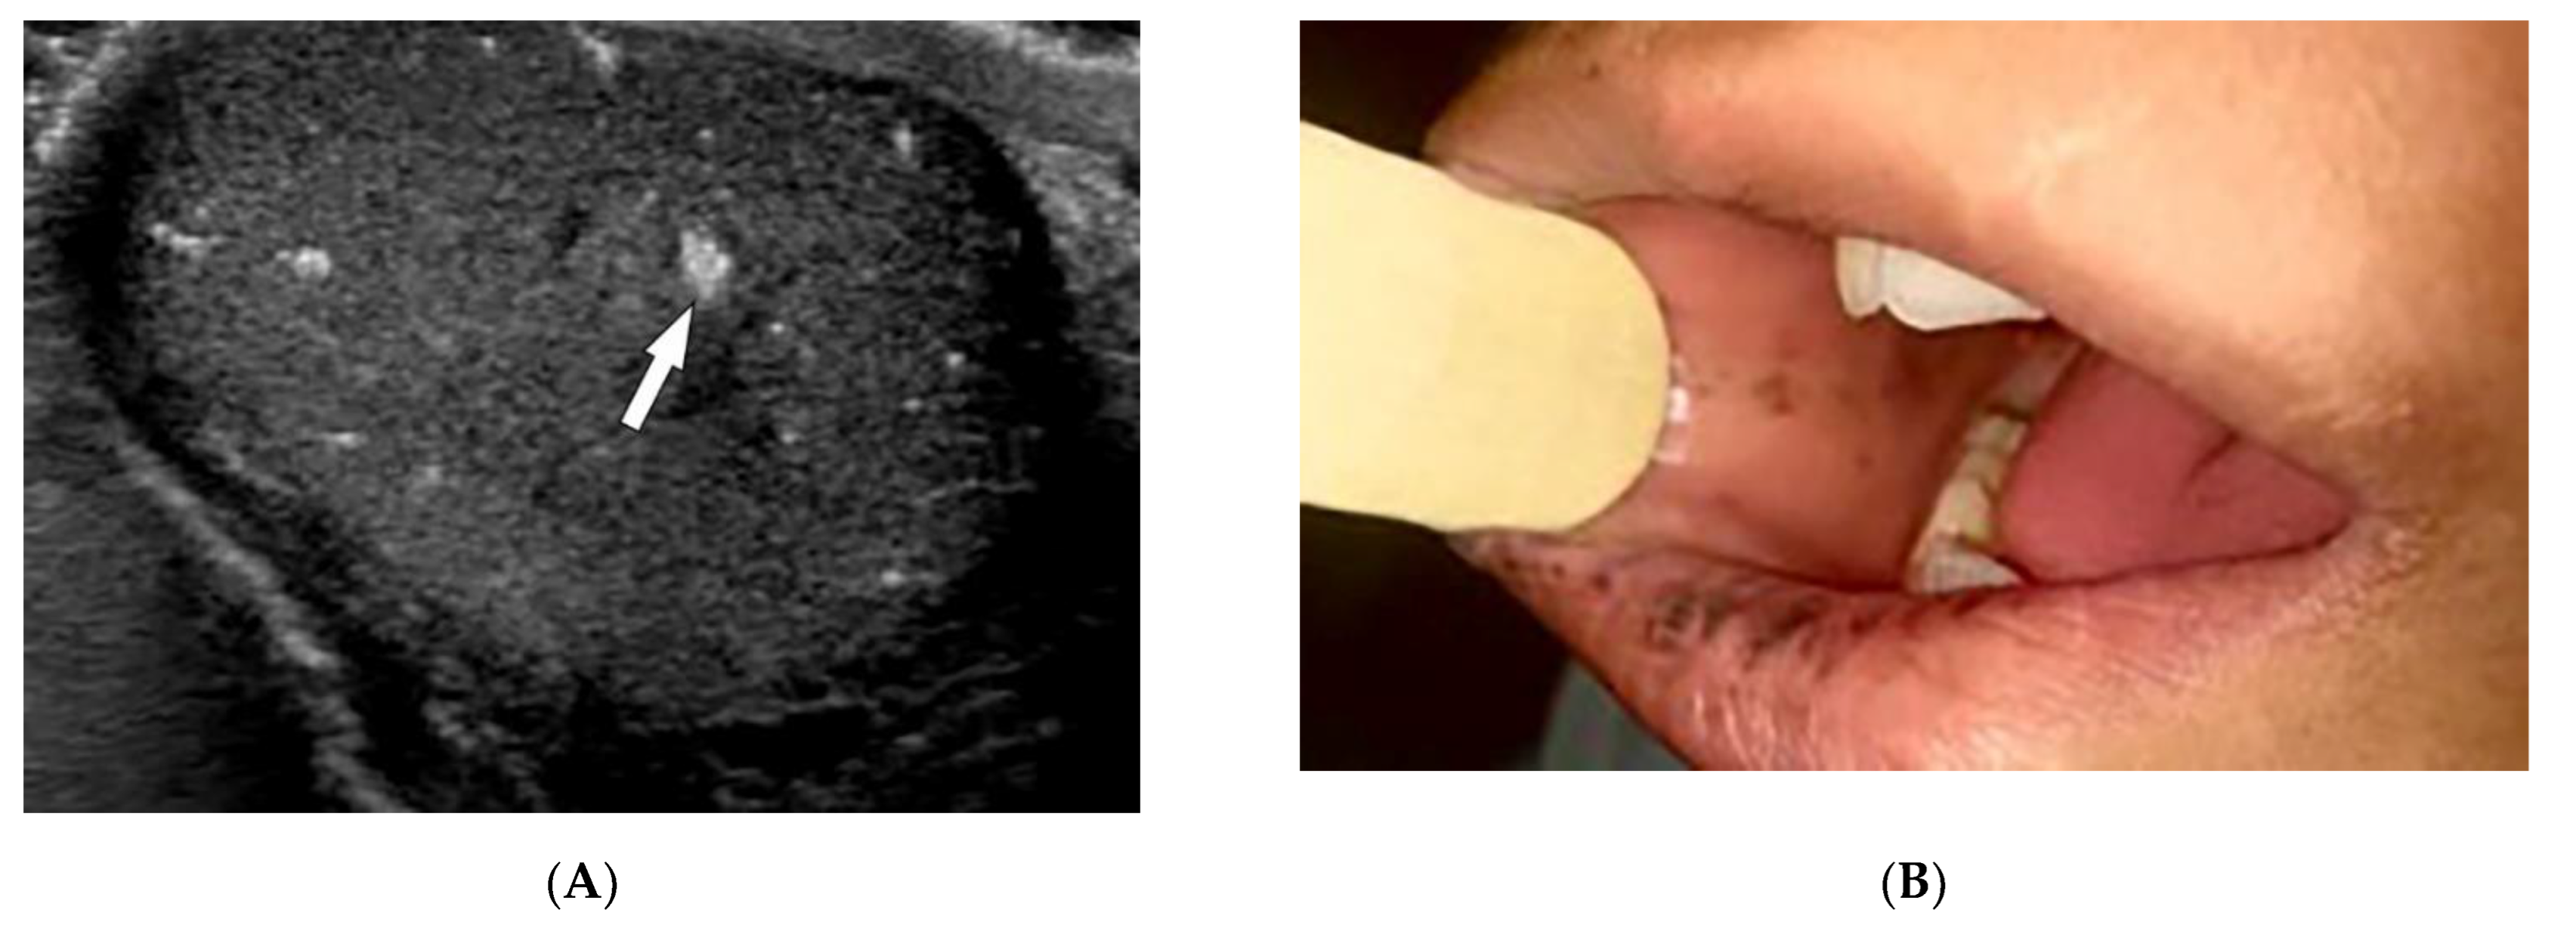

| Kaposi sarcoma | Erythematous or violaceous macules, plaques, nodules Pulmonary involvement Gastrointestinal involvement | Nodular enhancing masses Peribroncovascular nodules and halo sign |